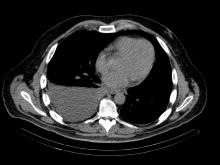

A 48-year-old man with a history of metastatic rectal cancer to the liver status post folfox and bevacizumab, proctosigmoidectomy, coloanal anastomosis, loop ileostomy, hepatectomy segment VI, hepatic ablation of segments V and IVb, and hepatic artery infusion pump placement with FUDR. Seven months after pump placement, thoracic surgery was consulted regarding a recurrent right pleural effusion (Image 1).

Image 1: CT Chest

IMPRESSION: Moderate to large right-sided pleural effusion.